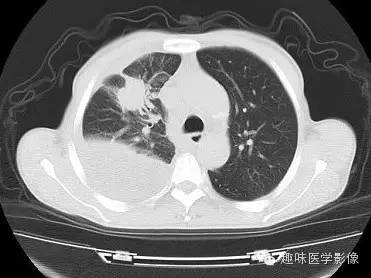

男,59岁,咳血待查。

CT: 右侧胸廓缩小。右肺上叶前段结节,略分叶,可见长短不一毛刺,胸膜牵拉征及血管集束征,右肺组织向肺门萎陷,左肺清晰,未见异常。纵隔内见淋巴结肿大(4R淋巴结增大)。右侧前壁及侧后胸壁包裹性积液征象。

右上肺周围型肺癌,纵隔淋巴结转移,胸膜腔包裹性积液。

3)空泡征是肺癌典型的CT影像,肿瘤直径小于3cm时,瘤体中央会出现多个1-2mm大小的点状低密度影,或多个影像融合。同时伴有纵隔、胸膜的转移,本例CT上可见4R淋巴结增大,胸膜腔包裹性积液。